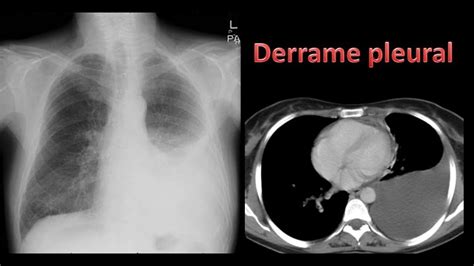

Entre las complicaciones están el derrame pleural, absceso pulmonar y bacteremia.